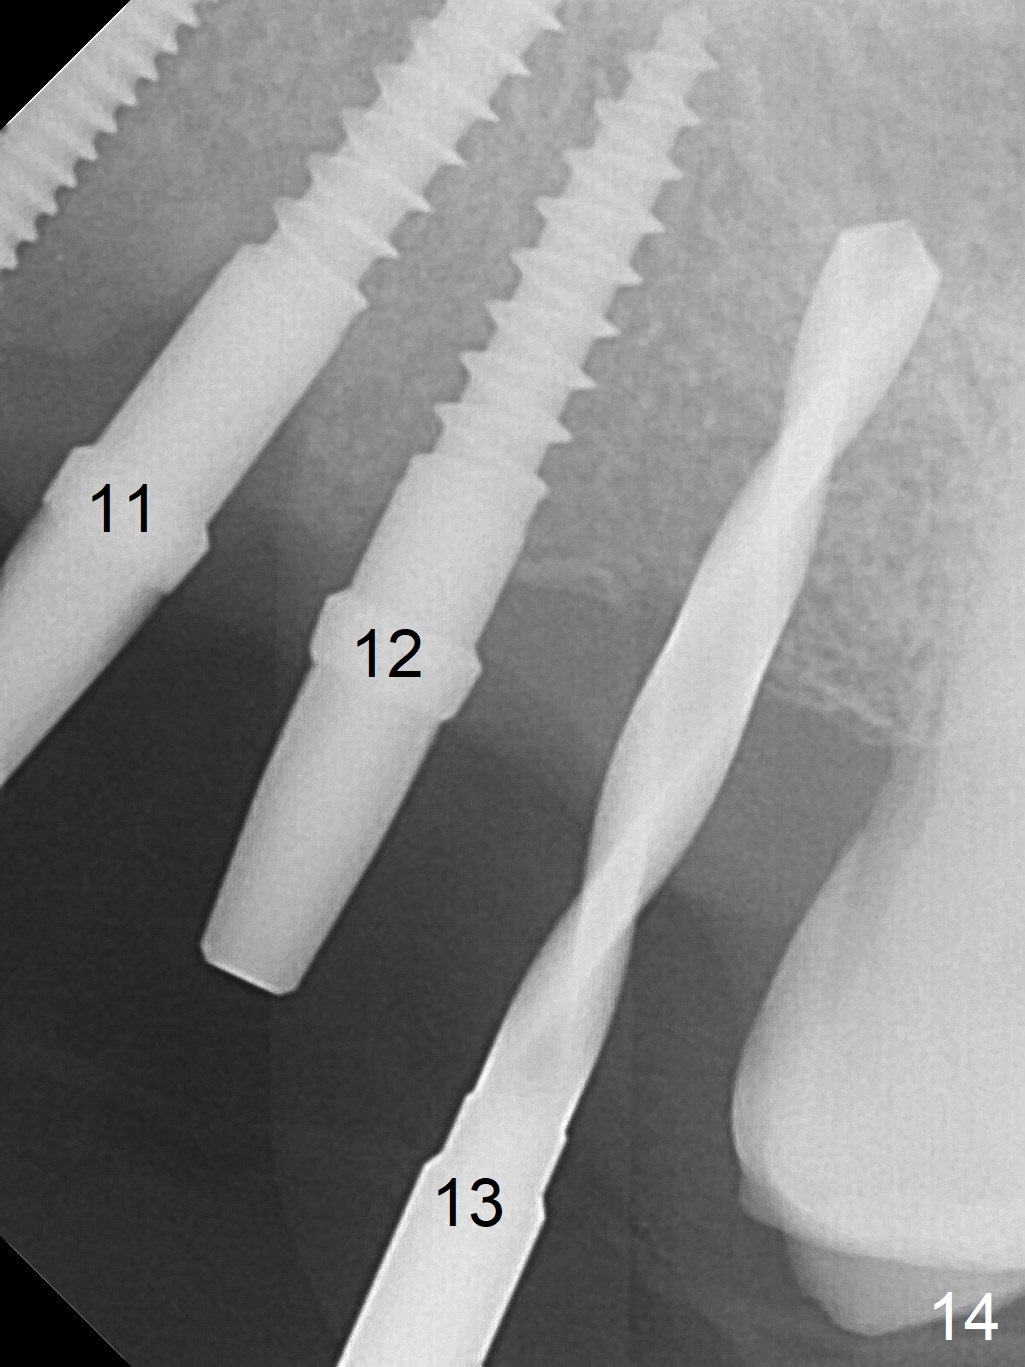

At the sites of #11 and 12, the knife-edged ridge is trimmed prior to initiation of osteotomy (Fig.12,13). With the flattened ridge, it is easy to start osteotomy and control the mesiodistal position. When the position and the trajectory are not correct, they can be changed (Fig.14-16) with 2.5x14(4), 2.5x12(2) and 3x10(2) mm implants placed at #11,12, and 13, respectively. With relatively correct position of each implant, it would be easy to fabricate a splinted 6-unit provisional.